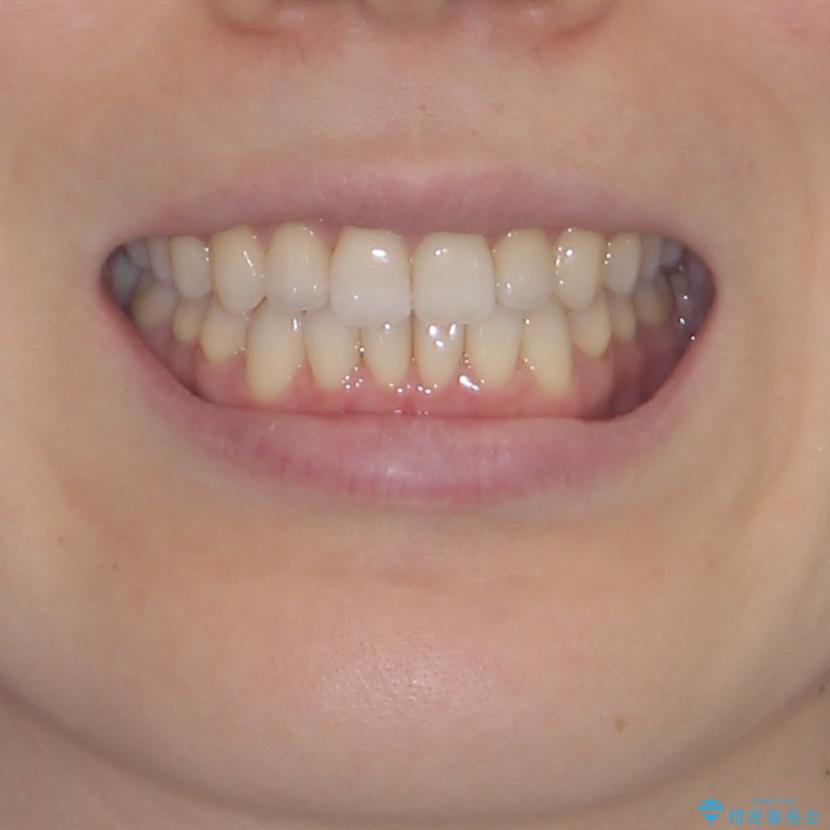

前歯の叢生とオープンバイト インビザラインでの矯正治療

- 前歯の開咬を気にして来院された患者様です。

オープンバイトは舌の突出癖により誘発され、治療後も突出癖が残っている容易に後戻りしてしまいます。

治療期間を短縮するためにも、舌突出癖の改善が極めて重要となります。